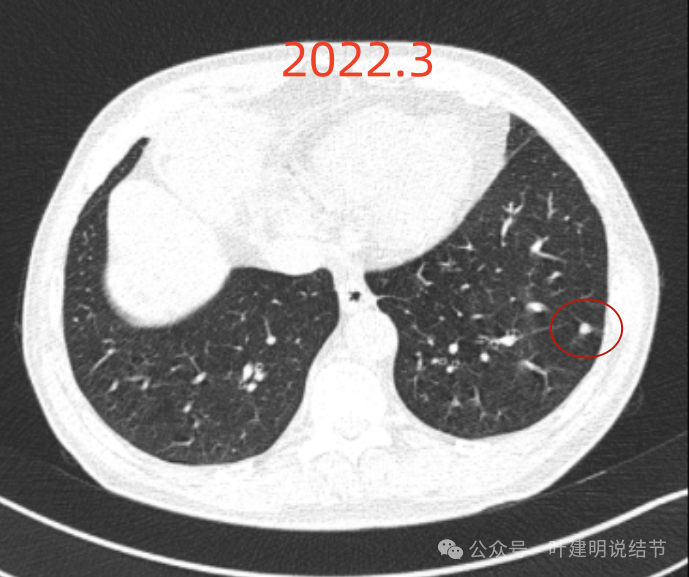

再看2024年6月时的影像:

右上没有明显变化,仍考虑良性可能性大。

左下也考虑良性,与2022年无明显变化。

右下新增病灶,混合密度,整体轮廓较清,瘤肺边界欠清。

有小血管进入,边缘毛糙。

局部有毛刺,但不够锐利;病灶感觉有一层晕似的,邻近胸膜下也有淡磨玻璃影。

实性密度为主,周围少许很淡的磨玻璃影。

边缘不平有毛刺,但不锐利;贴着胸膜但无明显牵拉。局部表面有浅分叶似的,但总体膨胀感不够。

病灶表面不光滑,边上有晕,邻近有淡磨,贴着胸膜无牵拉。

病灶边缘欠清晰,瘤肺边界稍模糊。较宽的基底贴着胸膜。

病灶有血管进入,有浅分叶,实性为主,邻近胸膜有片状淡磨玻璃影,近胸膜无牵拉。但有一定膨胀性。

病灶实性,与血管关系较为密切。

血管走向病灶,但似乎没有被病灶影响,有向内侧的分支甚至没有哪怕一点凹向病灶侧。整体显得偏模糊。

边缘区域杂乱,边糊。